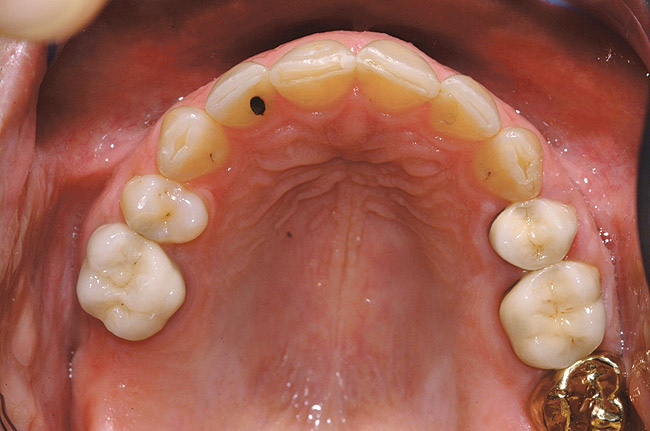

Fig 6 (and Fig 7). Prerestorative orthodontics was completed in 5 months. Final result 3 years, 4 months after completion.

Figure 6

Fig 7 (and Fig 6). Prerestorative orthodontics was completed in 5 months. Final result 3 years, 4 months after completion.

Figure 7